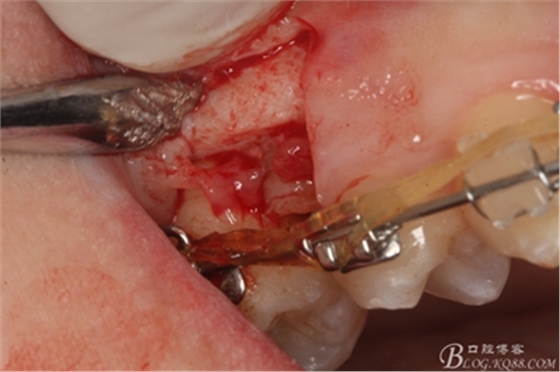

圖11.仔細考慮之后,在14頰側(cè)做垂直切口,切口長度僅達膜齦聯(lián)合處,做小切口。

圖12. 做垂直切口+齦溝內(nèi)切口,形成角形瓣,暴露出15根面。

圖13. 用小球鉆去除約1mm牙槽骨,暴露15牙根面約5mm。